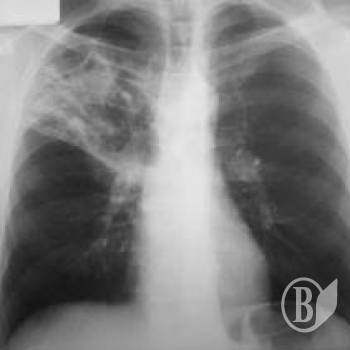

За 9 місяців поточного року медики зареєстрували в області 519 випадків захворювання на туберкульоз. 16 хворих – діти.

Майже 30% туберкульозу легень виявляється вже при розпаді легеневої тканини.

У 12-ти районах області відмічено зростання захворюваності, а у 5 з них ситуація критична. Це Куликівський, Варвинський, Козелецький, Борзнянський та Ічнянський райони.